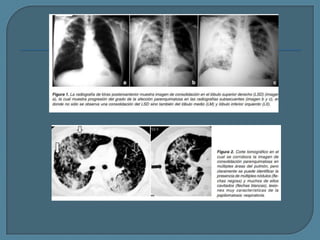

Radiografía simple (A) y TC (B) muestran una gran

masa maligna que mide más de 3 cm.

Radiografía anteroposterior (A) y TC (B) muestran un nódulo de 1.5 cm de aspecto

benigno - granuloma calcificado